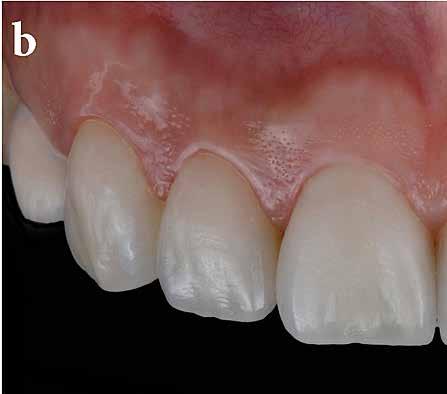

Az oxigén inhibíciós réteg kialakulásának elkerülése érdekében a kerámiafelszíneket glicerin géllel (Liquid Strip, Ivoclar Vivadent, Schaan, Liechtenstein) borítottuk, majd ezeket a felszíneket ismét 20-20 másodpercen keresztül világítottuk. A végeredmény megfelelt a páciens esztétikai igényeinek (6. a. ábra). Az átadott restaurátumok épségének megőrzése érdekében, a páciens számára éjszakai fogvédő sín készült. Az ötéves kontroll alkalmával megállapítottuk, hogy az elvégzett kezelésünk továbbra is sikeresnek tekinthető (6. b. ábra)

Az általunk alkalmazott adhezív rendszerek hatékonyságát nagymértékben növelhetjük azáltal, hogy a fogakat minimál invazív módon, azaz csak zománcon belül preparáljuk, és a kerámia héjakat kofferdám izolálásban ragasztjuk. Jelen esetismertetésünknek az volt a célja, hogy bemutassuk, hogyan lehet az adekvát módon kivitelezett kofferdám izolálással megelőzni

a munkaterület nyállal, vérrel vagy szulkusz-váladékkal történő kontaminációját. A megfelelő méretben kialakított perforációs nyílások és köztük lévő optimális távolság elengedhetetlen ahhoz, hogy a kofferdámot ideális módon tudjuk felhelyezni. Ezzel az esettel azt is bizonyítjuk, hogy a gumilepedő levegőfújással, fogselyemmel és teflonszalagok segítségével történő beforgatásával az ínyvérzés kialakulását el lehet kerülni. Ismételten szeretnénk hangsúlyozni, hogy a megfelelő kofferdám kapcsok használata nélkül nem tudtuk volna a preparált csonkszélt a gumilepedő szélétől eltartani. A kezelés során elért eredményeket jól alátámasztotta, hogy a páciens az ötéves kontroll vizsgálat során teljesen elégedett volt.